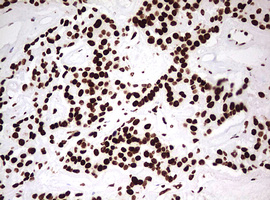

Immunohistochemical staining of paraffin-embedded Adenocarcinoma of Human endometrium tissue using anti-HNRNPM mouse monoclonal antibody. (Heat-induced epitope retrieval by 10mM citric buffer, pH6.0, 120°C for 3min, M06017-2)